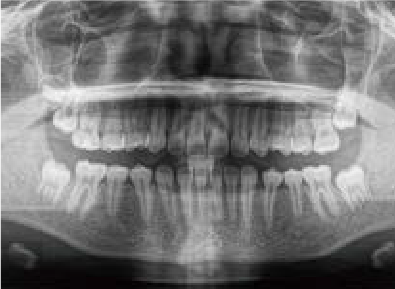

Jさん (矯正開始時:8歳)

Before

After

歯がガタガタに並んでいて、前歯の真ん中の位置が少し左にずれていました。

奥歯が生えるためのスペースが足りず、永久歯が生えて来られない状況が確認できました。

また、飲み込むとき下くちびるに力が入ってしまうクセが見られ、お顔全体の成長が遅れている様子が確認できました。

治療を終えて

歯がきれいに生えるためのスペースをしっかり確保することができ、歯並びを乱していたお口のクセも改善されたため、奥歯が生えるスペースを確保することができました。

しっかり噛めるかみ合わせを作ることが、将来の健康につながるので「よく噛む」練習も続けてもらっています。

主訴・治療内容 歯がガタガタになってきたことに悩み、無料相談に来院されました。

治療期間 3年

費用 462,000円(税込)